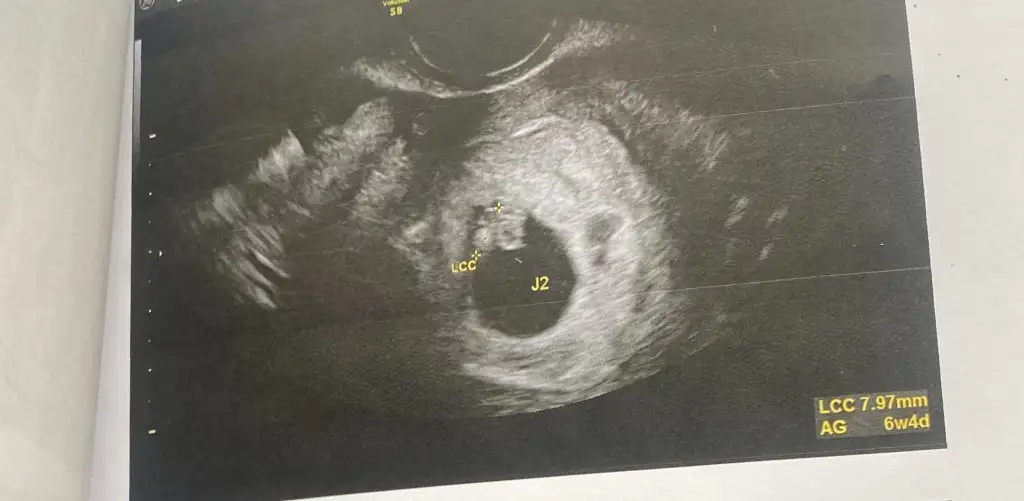

Merhaba 6+5 çift yumurta ikizleri (iki ultrasonda ayrı )vajinal muayane 3. Fotoda iki kese görünüyor